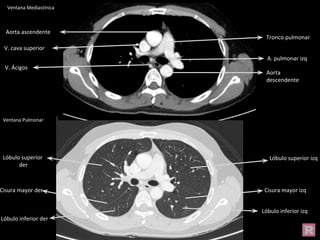

Aorta ascendente

Tronco pulmonar

V. cava superior

Aorta

descendente

A. pulmonar izq

V. Ácigos

Ventana Mediastínica

Ventana Pulmonar

Cisura

mayor der

Lóbulo superior der

Lóbulo inferior der

Lóbulo superior izq

Lóbulo inferior izq

Cisura mayor izq